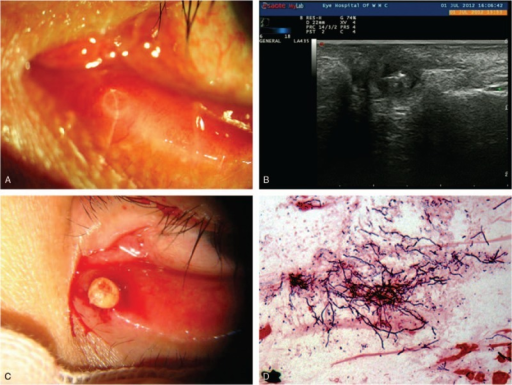

Canaliculitis의 진단 단서: "pouting" punctum(눈물점이 부어올라 튀어나온 모양) + 눈물점 압박 시 황색 결석/분비물 배출.

- Pouting punctum: 눈물점이 약간 부어오른 모양

- 압박 시 황색 결석(concretion)/농성 분비물 배출

- "Sulfur granule" (Actinomyces)

- 세극등검사: pouting punctum, 눈물점 주위 염증

- 눈물점 압박: 결석/분비물 배출

- Sulfur granule: Actinomyces의 조직학적 특징